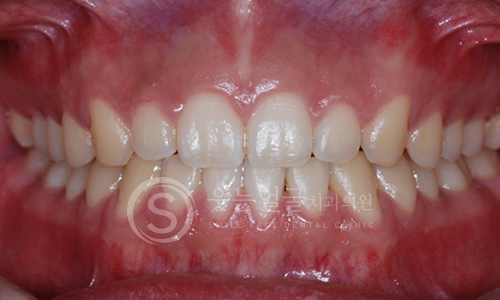

한눈에 보는

임플란트 전후사진